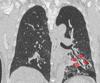

* ¿Qué estudio es? * ¿Qué patrón ves?

- TC - **Vidrio despulido** | (todavía se ven los vasos)